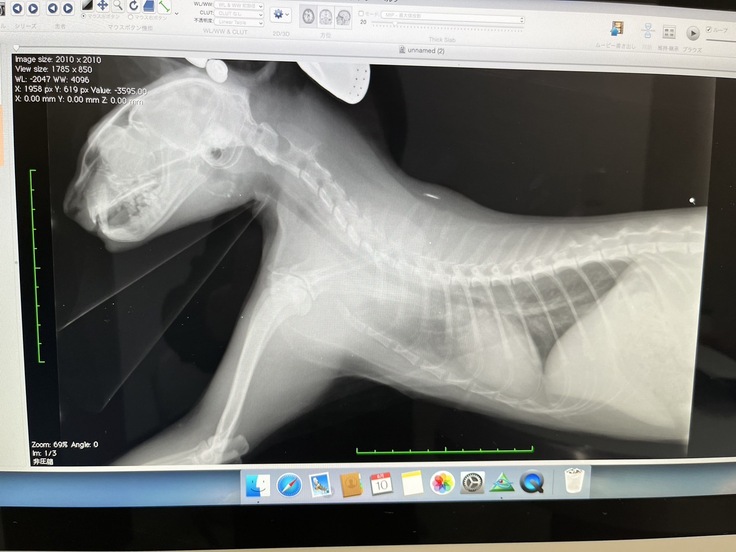

↓検査結果2枚・レントゲン2枚

↑診断書です。